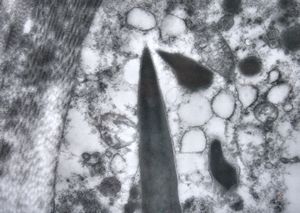

F,76y. | intranuclear needle-like structures - rhabdomyoma,tongue

F,76y. | intranuclear needle-like structures - rhabdomyoma,tongue